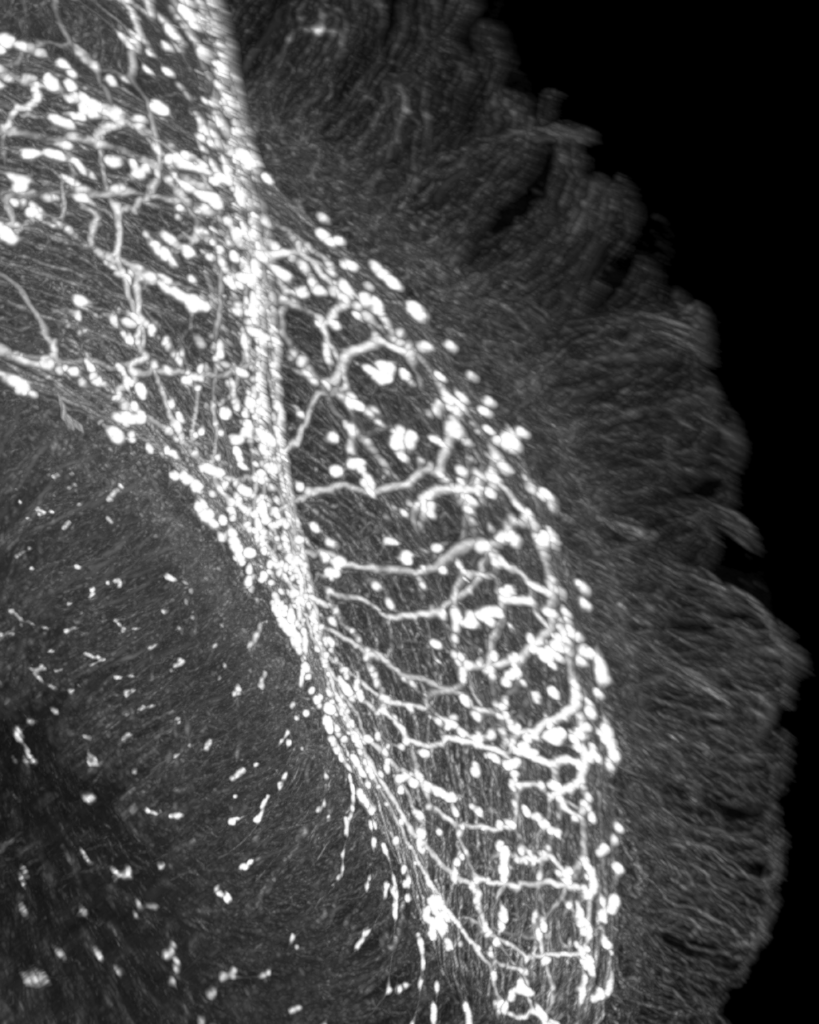

Forschende am Champalimaud Centre for the Unknown in Lissabon haben entdeckt, wie das Nervensystem im Darm entscheidet, ob das Immunsystem angreift oder repariert. Die Studie, veröffentlicht in „Nature Immunology“, beschreibt erstmals einen direkten Dreier-Dialog zwischen Darmnerven, den deckenden Epithelzellen und dem Immunsystem – und identifiziert dabei den Neurotransmitter VIP (vasoaktives intestinales Peptid) als zentrale Schaltstelle.

VIP wird von bestimmten Darmneuronen freigesetzt, wenn wir essen. Epithelzellen, die die Darmwand auskleiden, tragen den Rezeptor VIPR1 und empfangen das Signal. Je nachdem, ob VIPR1 aktiviert oder blockiert wird, produziert die Epithelzelle unterschiedliche Botenstoffe (Zytokine), die das Immunsystem in zwei gegensätzliche Programme lenken:

Tierversuche zeigten dramatische Effekte: Mäuse ohne VIPR1 in den Epithelzellen waren deutlich anfälliger für bakterielle Infektionen wie Salmonella, aber besser gegen Parasiten geschützt. Das Nervensystem im Darm fungiert damit wie eine Weiche, die je nach Situation den passenden Immunweg wählt.